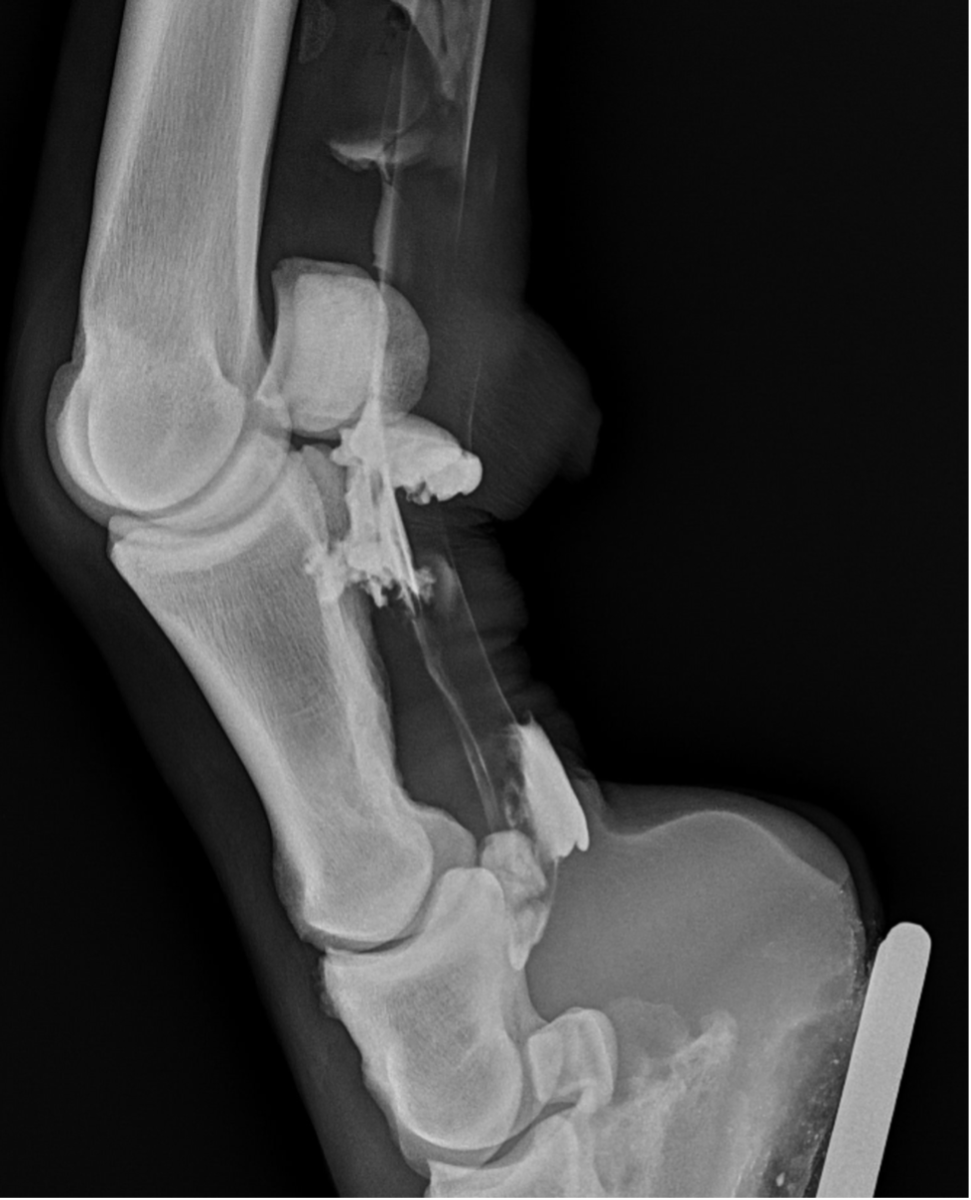

Upon further examination, contrast radiographs and ultrasound scans failed to identify any significant abnormalities apart from swollen synovium within the DFTS. To address this issue, our veterinary team administered 5mg of triamcinolone acetonide along with 20mg of HA, complemented by a compression wrap. Subsequently, the horse underwent a two-week confinement period in a small yard, followed by gradual reintroduction to exercise through 10 minutes of hand walking twice daily, with the distal limb wrapped for additional support.